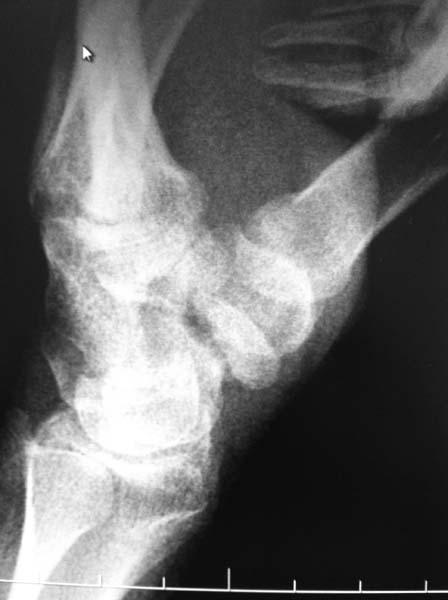

[Ortho] Ложный сустав ладьевидной кости

Уважаемые коллеги! Выскажете свое мнение по тактике лечения.

2ая проекция